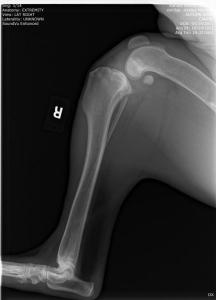

UPDATE: I know I have much to update in BHRR's Autumn's blog and before I go to bed in the wee hours; I shall update her blog plus add photos from her x-rays – taken of both legs, chest, back, legs, heart etc. on October 24th, 2012 and you can find them below! 🙂

From there, we are putting our creative hats on as she will need two cruciate surgeries – $6,000-$7,000+ – and the specialist is still looking at those eyes and what is going to be best….

She has three surgeries ahead of her – a spay and two separate cruciate surgeries and this is in addition to her almost $3,000 bills to date that have been racked up.